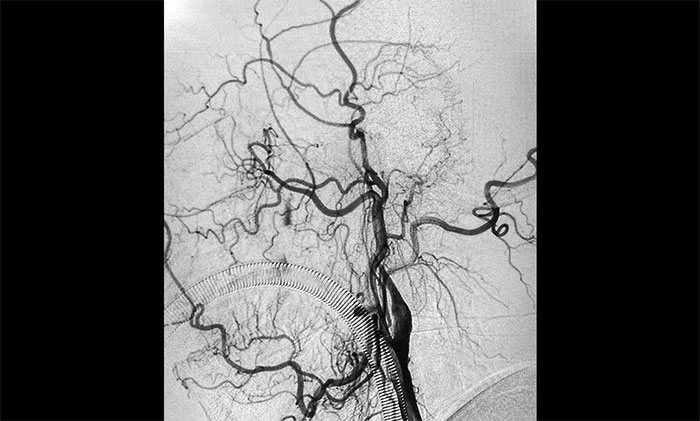

▲术前DSA影像:左侧颈内动脉眼动脉段以远闭塞

术中脑血管造影可见:左侧颈内动脉眼动脉段以远闭塞……余血管未见明显异常。张琪博士在刘春、周林华、李喆医生协助下,通过右侧股动脉穿刺,将微导管、微导丝送达左侧大脑中动脉M1段,经多次抽吸+支架拉栓,顺利取出血栓。造影显示,颈内动脉眼动脉段血流恢复。